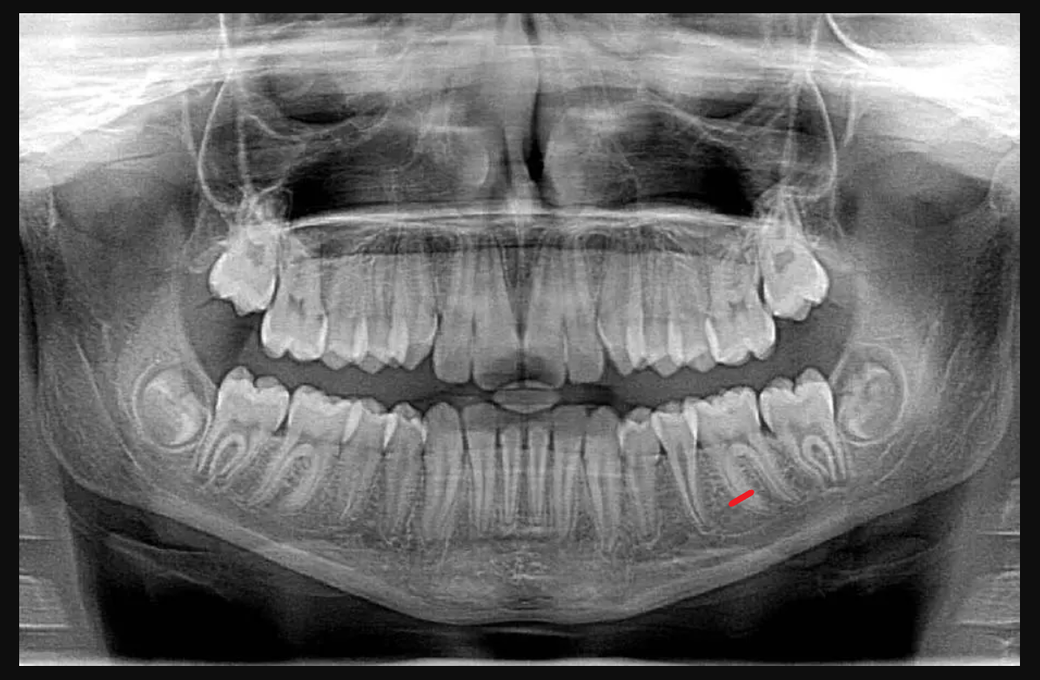

(위의 사진은 제 치아사진은 아니고 예시를 들기 위한 사진입니다.)

2년전 빨간색으로 표시한 어금니 부분에 치아파절이 생겨서 크라운 치료를 받았습니다.

그것에 더해 (사진에 표시한) '치아 뿌리부분에 금이 갔는지 아닌지 확실하지 않는데 다음주에 신경치료를 시작하기전, 사진을 한번 더 찍어보고 치료를 결정해보겠다.' 하여 다음주에 다시 방문하여 사진을 찍었습니다.

첫번째로 찍었던 사진에서는 희미했던 것이 두번째로 찍었던 사진에서는 위에 표시한 뿌리부분이 살짝 벌어진게 보였고 이부분을 설명하면서 '여기서 크라운 치료를 계속할지, 중단할지 본인이 선택하라'고 분명히 말했습니다.